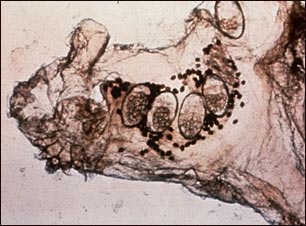

Microfotografía del ácaro de la escabiosis, los huevos y el ácaro en las heces

En esta microfotografía aparece el ácaro responsable de la sarna, junto con sus huevos y heces. Los ácaros excavan túneles dentro de la piel, en donde depositan sus huevos y heces. La infestación por sarna produce un prurito intenso que induce al rascado y produce lesiones en la piel (excoriaciones). Sin tratamiento, la enfermedad puede perdurar por muchos años, razón por la cual ha sido llamada "prurito de los siete años".